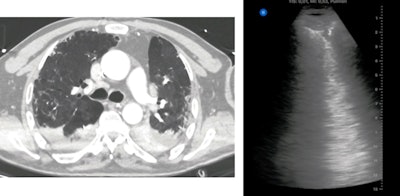

CT is considered the gold standard for COVID-19 chest imaging due to its incredible sensitivity and specificity, but it also exposes patients to radiation and has infection control challenges. Although multiple studies have proposed using ultrasound as an alternative to CT, no prior studies have compared the effectiveness of the two modalities for COVID-19.

All patients in the study also underwent chest CT scans, which were read by two radiology trainees under the supervision of a senior radiologist. The radiologists calculated a total CT severity score, and like with a LUS, a higher CT severity score represented more severe lobar involvement.

Out of the 51 patients in the study, 37 patients had findings suggestive of COVID-19 on CT and 40 had COVID-19-like findings on ultrasound. Statistical analysis revealed significant agreement between lung ultrasound and CT findings, including an ultrasound sensitivity of 100%, specificity of 79%, and positive predictive value of 93%.